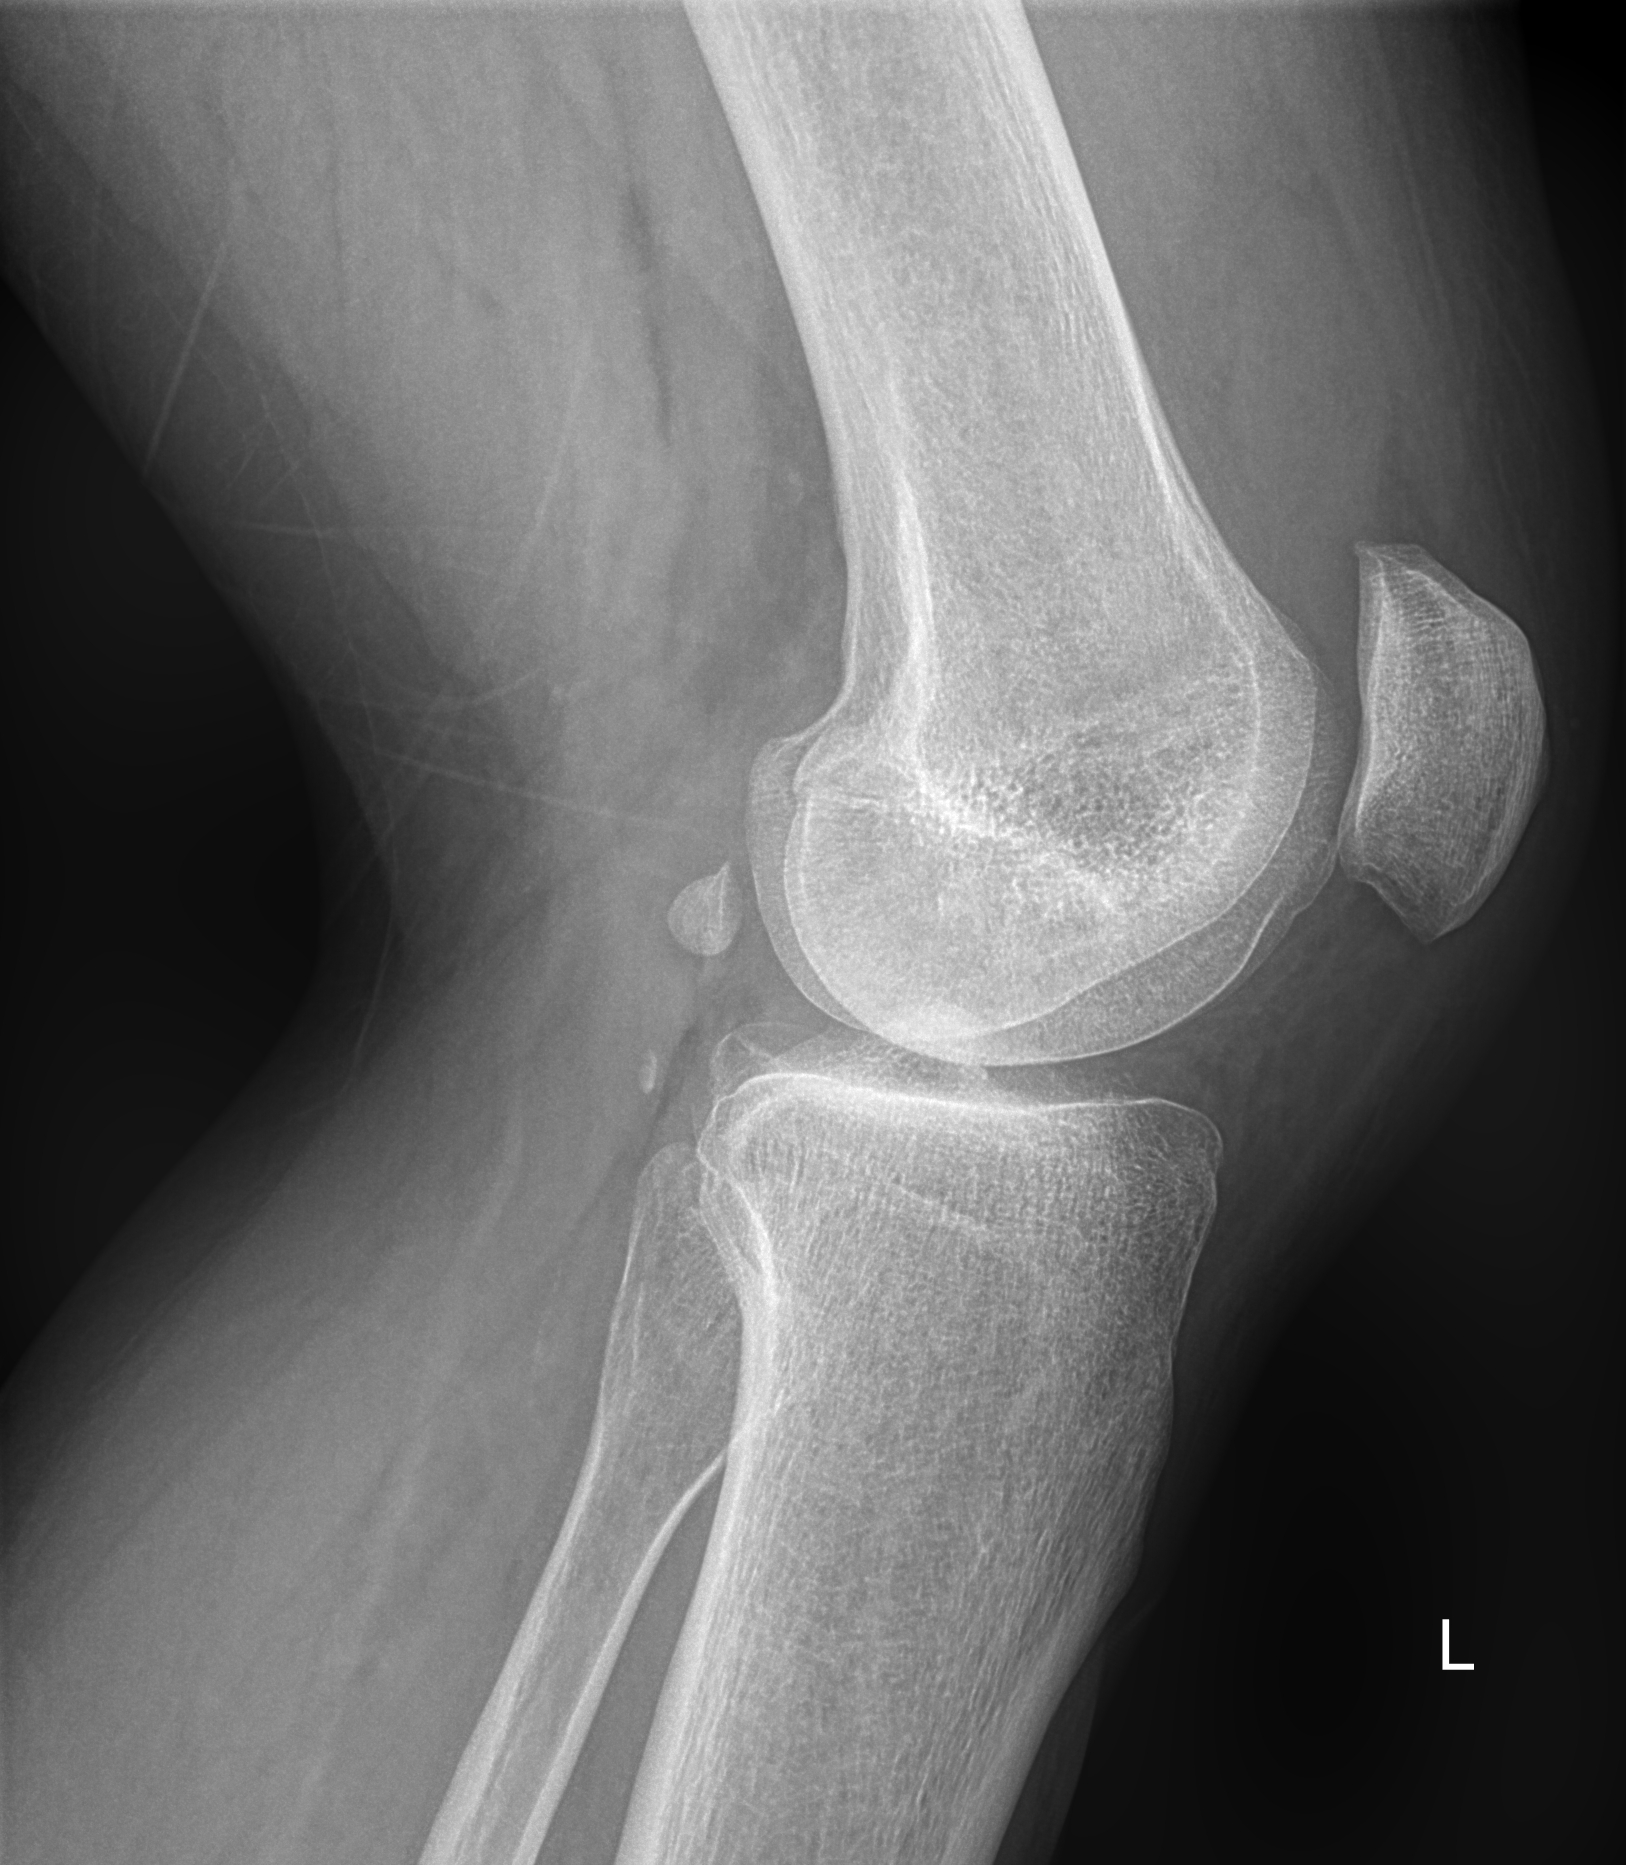

-коленный сустав (травмы мениска, переломы, изменений в кости и суставе);